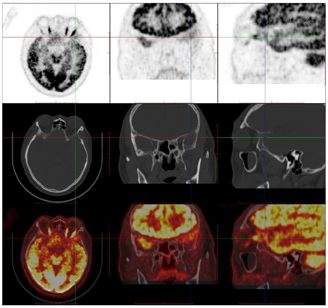

头颅顶可见术后瘢痕,愈合可,后颈可见一长约10 cm术后愈合瘢痕。头颅压痛、包块。发病来,患者神志清,精神可,睡眠可,饮食及大小便正常,体重无明显变化。2021年10月8日行PET-CT示左侧额顶部颅骨术后改变;左侧颞极片状高密度影并邻近骨质破坏,代谢增高(图A);左前纵膈肿块,代谢增高(图B);双肺散在结节,代谢轻度增高(图C);右侧锁骨、左侧第6肋,胸9-腰1、3椎体及其附件骨、双侧髂骨及双侧股骨近端多发混合型骨质破坏,代谢不同程度增高,考虑多发转移瘤(图D,图E,图F);2021年10月10日复查CT示右肺下叶可见结节影,直径约1.5 cm,增强扫描轻度强化;前上纵膈可见类圆形软组织密度影,边界清楚,大小约4.4 cm×3.3 cm,增强扫描轻度强化。于2021年10月11日在局部浸润麻醉下行CT引导下经皮纵膈占位穿刺活检术。病理结果示:肺穿刺组织内见恶性肿瘤,符合转移性间变性脑膜瘤。2021年10月13日MRI示:多发胸椎椎体及附件、所扫及L1椎体异常信号,结合病史,考虑为转移瘤可能。